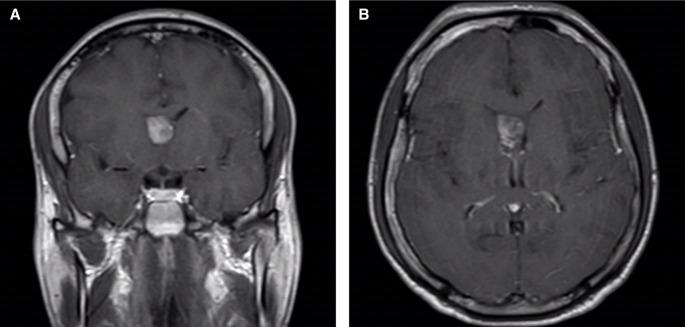

一名法医精神病住院患者的偶然性脉络丛乳头状瘤:病例报告。

Incidental choroid plexus papilloma in a forensic psychiatric inpatient: a case report.